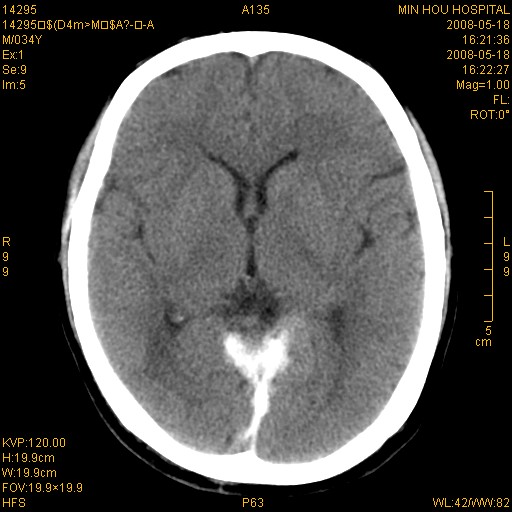

标题: CT13617:双顶叶白质水肿伴大脑镰小脑幕广泛钙化 [打印本页]

标题: CT13617:双顶叶白质水肿伴大脑镰小脑幕广泛钙化

双侧侧脑室后脚旁对称性低密度影,符合肾上腺白质营养不良(成人型)改变    小脑幕及大脑廉钙化  可考虑为生理性

支持:1、肾上腺白质营养不良.2、小脑幕、大脑镰广泛钙化。3、建议进一步检查。

硬脑膜钙化是主因,双侧顶叶白质密度减低是可能由于静脉路回流受阻所致。